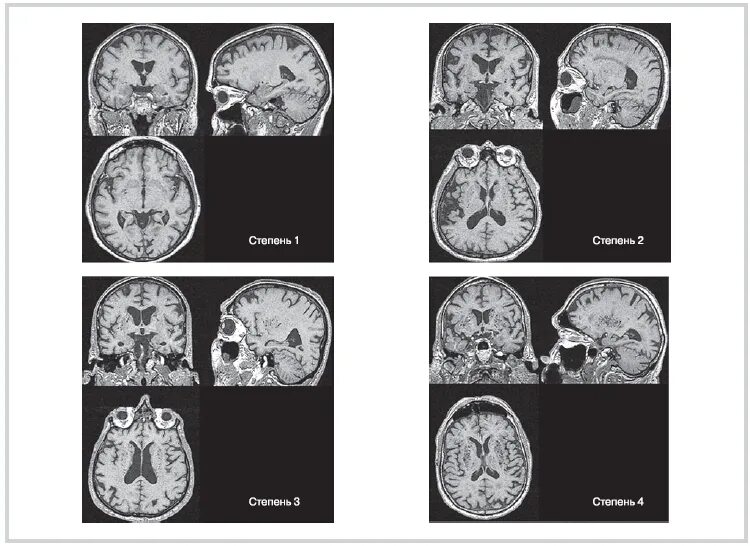

Что значит пространства вирхова робина